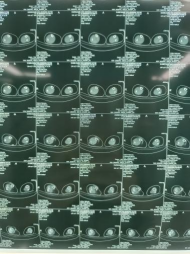

患者男性,54歲,外傷致右側(cè)脛腓骨開放性骨折8小時,局部可見右側(cè)脛骨骨折近端露出,小腿部肌肉部分損傷外露,皮膚損傷,脛神經(jīng)損傷。CT顯示右側(cè)脛腓骨遠(yuǎn)端粉碎骨折,累及關(guān)節(jié)面,骨折斷端分離移位,成角移位。